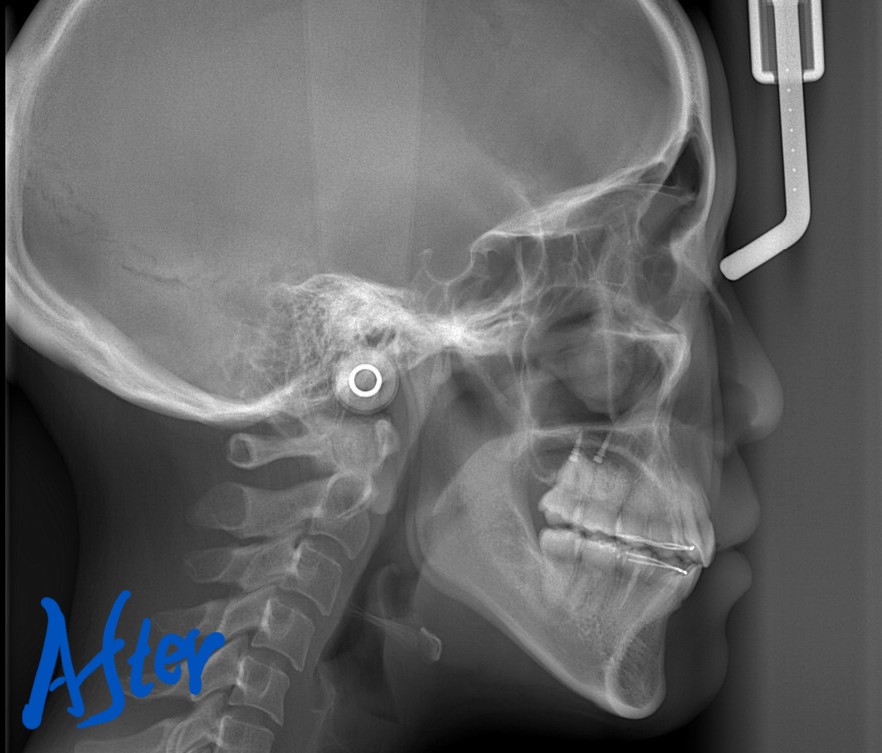

【After】

「もう十分です」という患者さんの声に許してもらいました

【治療期間】 2年3カ月間

【治療費用】 81万6千円

・スタンダードtypeのマルチブラケットシステム

・アンカースクリュー(2本)

・PLAS & パラタルバー

レントゲン写真でも矯正治療前後を比較してみましょう

口元がスッキリして、オトガイにあった梅干し状のシワもほぼ無くなりました

今回は、歯並びをきれいにすることが一番! 口元の変化はあわよくばを狙った二番!でしたが、

歯並びはもちろん、口元もスッキリさせることが出来ました。

お口を閉じるのも、とても楽になった!と合わせて喜んでもらいました。